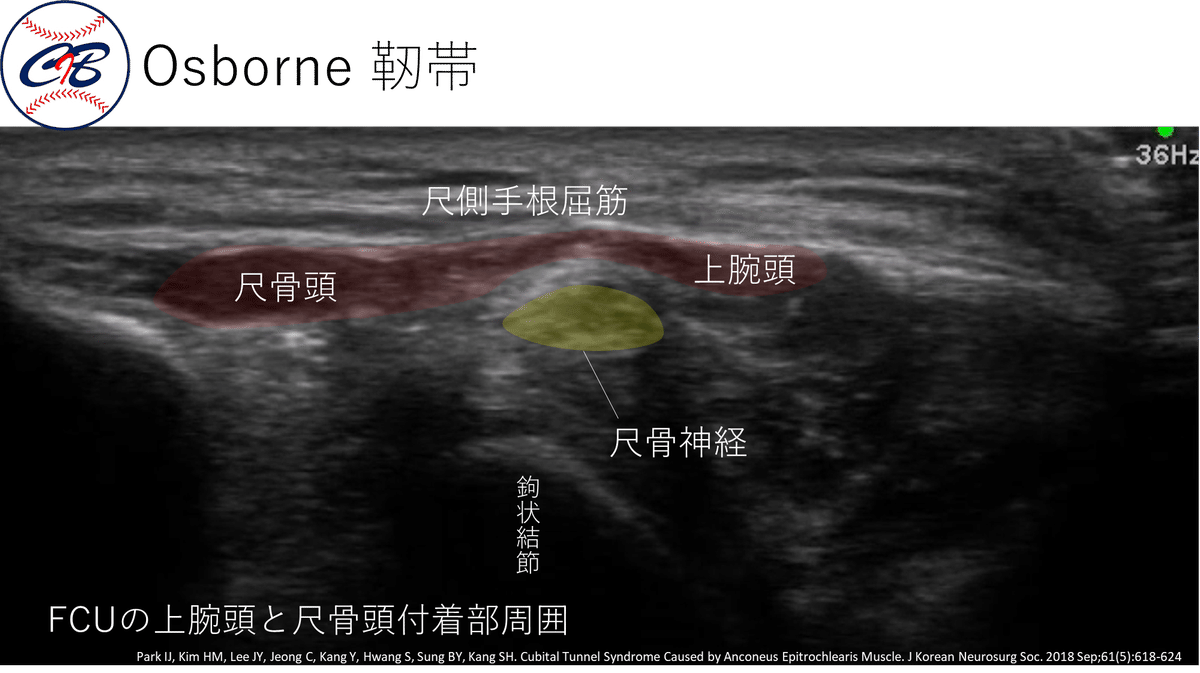

★各絞扼好発部位での Tinel sign~エコーでの見え方~

それぞれの部位がエコーでどのように診れるかを示していきます。

尺骨神経の肘部管の周囲には、3層構造が存在します。

この ”筋筋膜性3層支帯”(the myofascial trilaminar retinaculum:MTR) とよばれているものは、滑走性が重要であるといわれています。